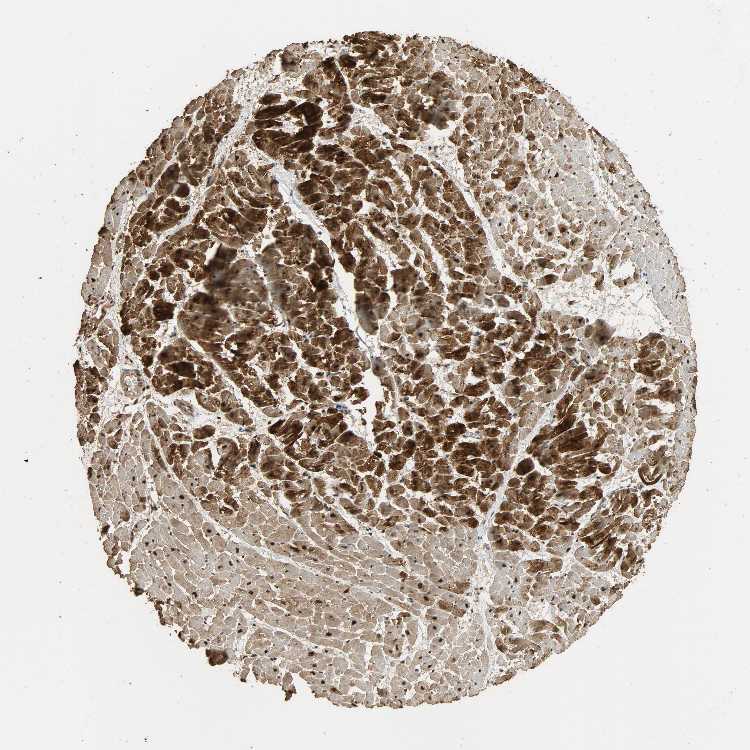

HEART MUSCLE - Antibody stainingi

Antibody staining in the annotated cell types in the current human tissue is reported as not detected, low, medium, or high, based on conventional immunohistochemistry profiling in selected tissues. This score is based on the combination of the staining intensity and fraction of stained cells.

Each image is clickable and will lead to virtual microscopy that enables deeper exploration of all samples and also displays staining intensity scores, fraction scores and subcellular localization as well as patient and tissue information for each sample.

Antibody HPA005559

Cardiomyocytes High